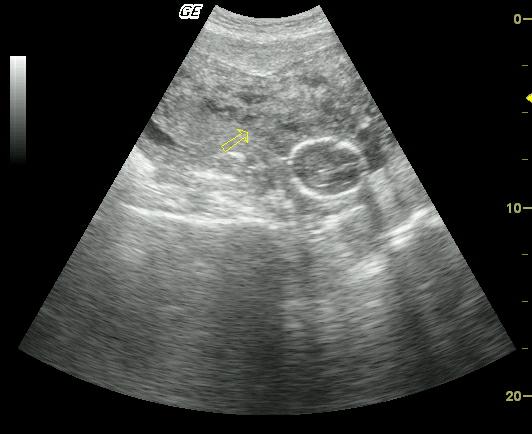

Эхоструктура этого слоя хорошо видна на УЗИ. Миометрий состоит из трех слоев. Основной продольный слой состоит из круговых мускулов. В некотором количестве также присутствуют и продольные мышечные волокна. Он связан непосредственно с периметрием, который покрывает его с наружной стороны органа.

В результате этого воспалительного процесса матка приобретает диффузно неоднородную структуру. Эти изменения можно выявить при исследовании, например, с помощью УЗИ, и именно на основании этих данных ставится диагноз.

При заболеваниях миометрий неоднородный. Он может быть отечным. На УЗИ видна диффузная неоднородность.

- УЗИ матки, при котором рассматривается эхоструктура органа, и при не типичности показаний выносится предварительный диагноз;